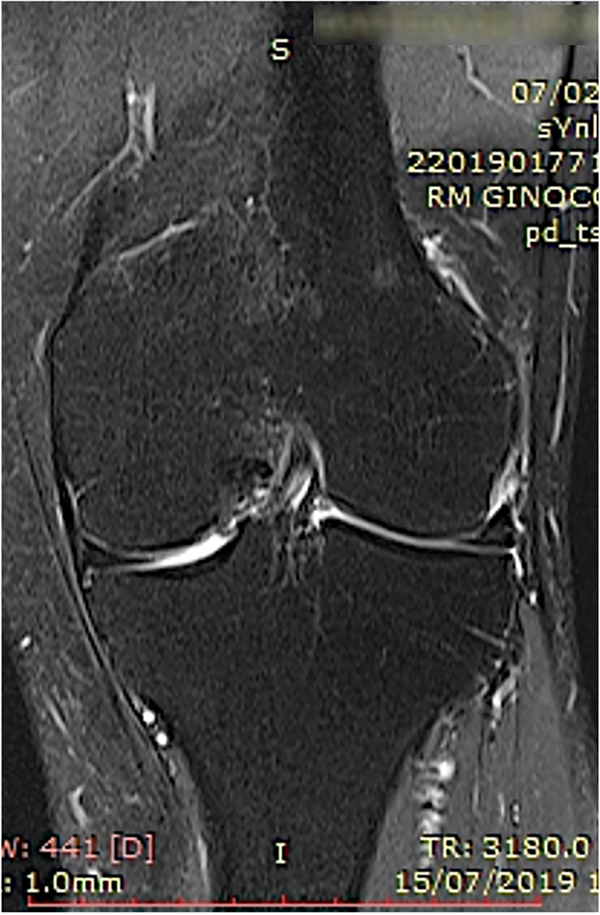

Un estudio clínico reciente concluye que el aumento biológico del hueso subcondral mediante esta técnica resultó en una reducción significativa del dolor y una mejor función articular con resonancia magnética que muestra la resolución de las LMO a los seis y doce meses de seguimiento (figs. 7 a 10).

Figura 10: Un ejemplo de caso de lesión del hueso subcondral en el cóndilo femoral medial de la rodilla tratada con osteocoreplastia. Doce meses después del tratamiento, vista coronal de la resonancia magnética de la rodilla.

El estudio actual destaca la importancia de tratar las LMO sintomáticas dirigidas al hueso subcondral para lograr el éxito.72